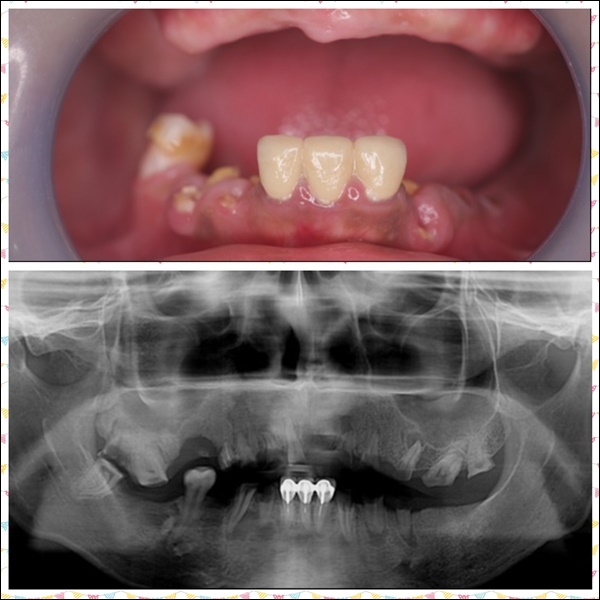

在拍攝X光片後,牙醫師針對媽媽牙周病這部分有特別說明,

媽媽因為牙周病導致牙床、牙肉、骨頭漸漸流失,在這樣的情況之下,

必須先完成牙周病治療、齒槽骨重建、補肉補骨手術,接著才能進行其他療程,

在多方考量下,我們一家決定讓媽媽以全口重建取代活動假牙,

在新全美牙醫師專業技術加上媽媽努力回診下,

媽媽牙周狀況終於已經可以施做全口重建~~